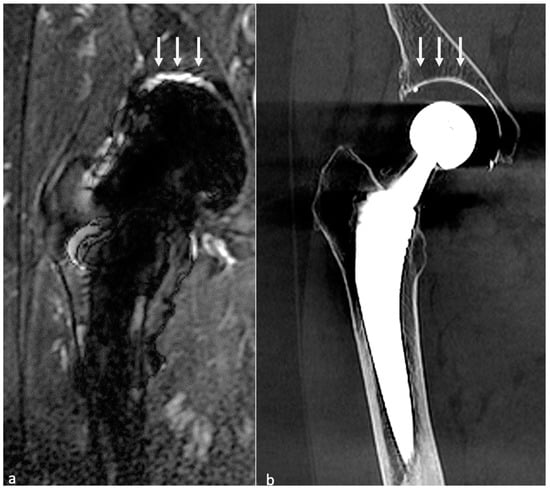

4.3.4. MRI

- Metallosis results from the shedding of metallic debris (secondary to a MoM prosthesis with corrosion, a conflict between a metallic acetabular cup and the prosthetic neck, or a contact between a metallic head and an acetabular metal back in case of PE wear or dislocation) that induces synovitis and an indolent pattern of osteolysis, potentially leading to loosening (i.e., potentially looking similar to osteolysis and PE wear). Synovitis may contain low-signal intensity or metallic density debris, causing MRI artifacts and bone erosion, best depicted on CT-MAR (Figure 20). Such debris might also be located in periprosthetic soft tissue and lymph nodes [54,57]. Metallic debris presence might also accentuate PE wear (i.e., third fragment wear) [54]. Of note, high serum metal-ion levels can be found in symptomatic and asymptomatic patients and would be associated with pseudo-tumors, so that such a biological finding should lead to the prescription of an MRI to rule out a pseudo-tumor even in asymptomatic patients [6,103].

- Additionally, referred to as trunnionosis, trunnion corrosion corresponds to a soft-tissue reaction to metal debris released from micromotion and mechanical wear at the head–neck or neck–stem junction of modular MoP HA. On MRI, it manifests as an adverse local reaction associated with medial calcar resorption [11,104].